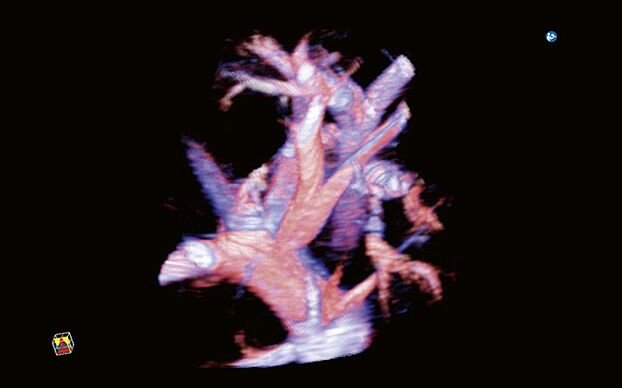

- Программно-технологический комплект 4D: рендеринг поверхности, визуализация полостей, мультипланарная реконструкция, MultiView для ультразвуковой томографии и ряд других функций

- Функция 3D Color

- Функция Fusion 3D для получения объемных изображений с поддержкой цветовых допплеровских режимов с помощью обычных датчиков

- 4D - объемное сканирование в реальном времени больше не фантастика, а впечатляющее достижение современных технологий. С помощью сканирования этого типа вы сможете рассмотреть даже самые мелкие детали изображения под любым требуемым для проведения исследования углом

- Функция получения трехмерного изображения в режиме цветового допплеровского картирования - функция поможет вам получить качественные трехмерные цветные изображения при проведении исследования. Нужного эффекта удается достичь за счет использования датчиков 3D/4D в В-режиме с последующим восстановлением объемной структуры в режиме ЦДК. Кроме того, данная функция совместима с режимом Freehand 3D